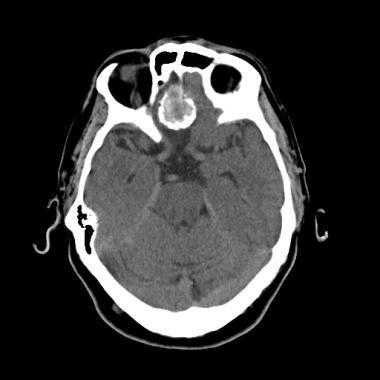

Внутривенное введение контраста помогает в оценке менингиомы: в более 90% случаев наблюдается интенсивное равномерное повышение плотности после введения контраста.

Неоднородный характер контрастирования может быть следствием некроза или, реже, кровоизлияния.

З адняя тенториальная менингиома на корональном КТ-изображении с контрастным усилением. К намету мозжечка прилежит объемное образование повышенной плотности с четкими краями. Визуализируются застой спинно-мозговой жидкости, легкий отек прилежащих тканей, гомогенный характер контрастирования, а также расширение желудочков.